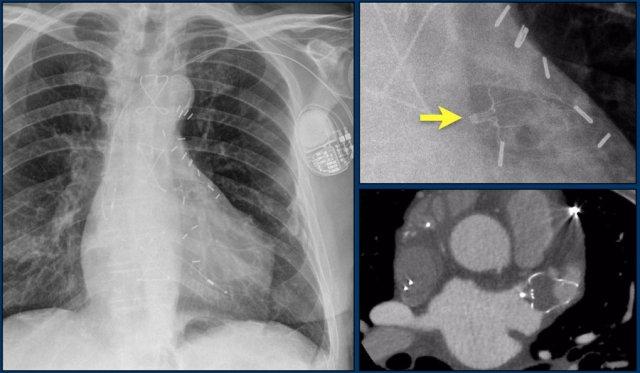

Các phát hiện bao gồm:

- Hai điện cực thượng tâm mạc kết nối với máy tạo nhịp

- ICD

- Hai điện cực đến mỏm thất phải

- Một điện cực chứa hai cuộn sốc điện

- Van ba lá (mũi tên)

- Van hai lá

Bệnh nhân này đã được sửa chữa ba van:

- Van ba lá

- Van động mạch chủ

Có máy tạo nhịp tim với điện cực thượng tâm mạc.

Phương án này được lựa chọn vì người ta cho rằng điện cực đặt theo đường thông thường vào thất phải sẽ ảnh hưởng quá nhiều đến chức năng của van ba lá nhân tạo.

Mũi tên trắng chỉ vào van động mạch chủ.

Mũi tên vàng chỉ vào van hai lá.